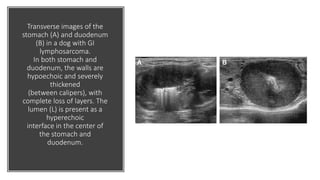

Transverse images of the

stomach (A) and duodenum

(B) in a dog with GI

lymphosarcoma.

In both stomach and

duodenum, the walls are

hypoechoic and severely

thickened

(between calipers), with

complete loss of layers. The

lumen (L) is present as a

hyperechoic

interface in the center of

the stomach and

duodenum.

Transverse images ofthe stomach (A) and duodenum (B) in a dog with GI lymphosarcoma. In both stomach and duodenum, the walls are hypoechoic and severely thickened (between calipers), with complete loss of layers. The lumen (L) is present as a hyperechoic interface in the center of the stomach and duodenum.